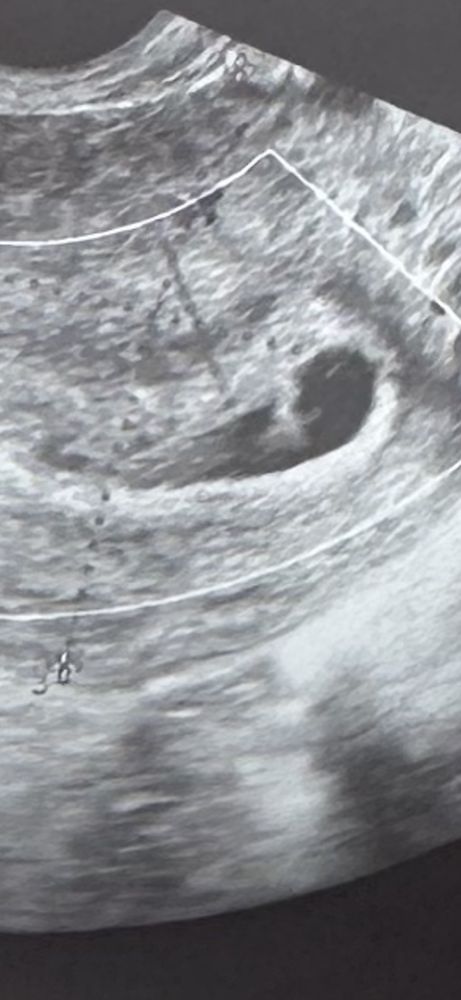

Анализы, скринингиДевочки, всем добрый день! Доктор в отпуске, а я в панике))) стимулировали овуляцию. Задержка и тесты полосатые. Хгч рос слабо. На узи сказали, что плодного яйца нет, но есть что-то не однородное. 2 желтых тела 22 и 24 размером с кровотами. Говорит вероятно плодное яйцо деформировалось и выйдет.

может кто-то сталкивался с таким желтым телом ?